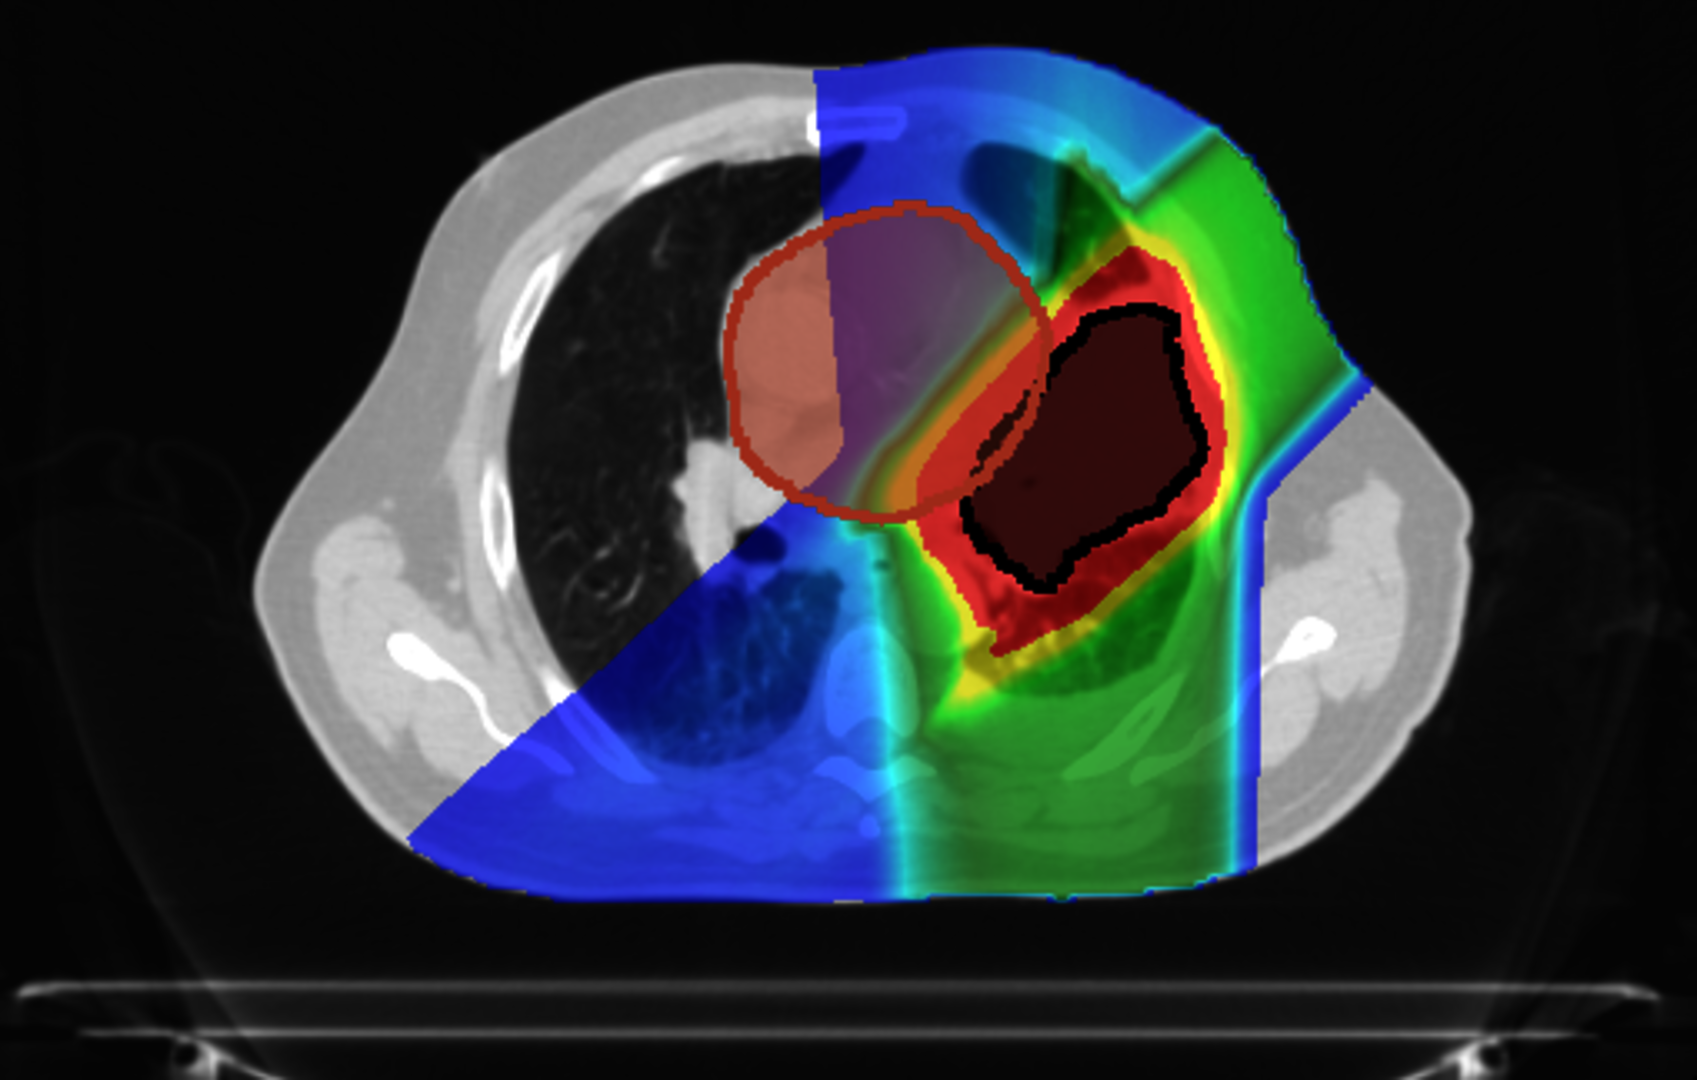

In addition, at GSI, we are leading the investigation of upright carbon ion therapy for lung cancer patients. In a collaboration with Northwestern Medicine Chicago Proton Center, we have conducted an extensive comparison of treatment plans between postures.